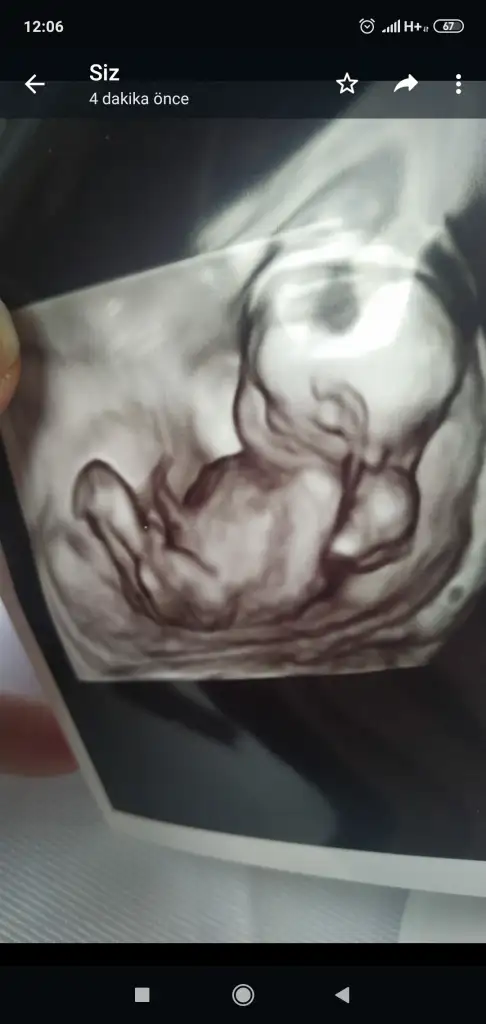

Asla uyanmadı küçük voldemort eli kafada kara kara düşüne düşüne uyuyoor.

17 cm 170 gram olmuş teyzelerii

Voldemort demenı basta anlamadım fotoyu gorunce cok guldum saglıkla gelsın mınnak yakında harry potter a donusur sekılden sekıle gırıyolar😂😂